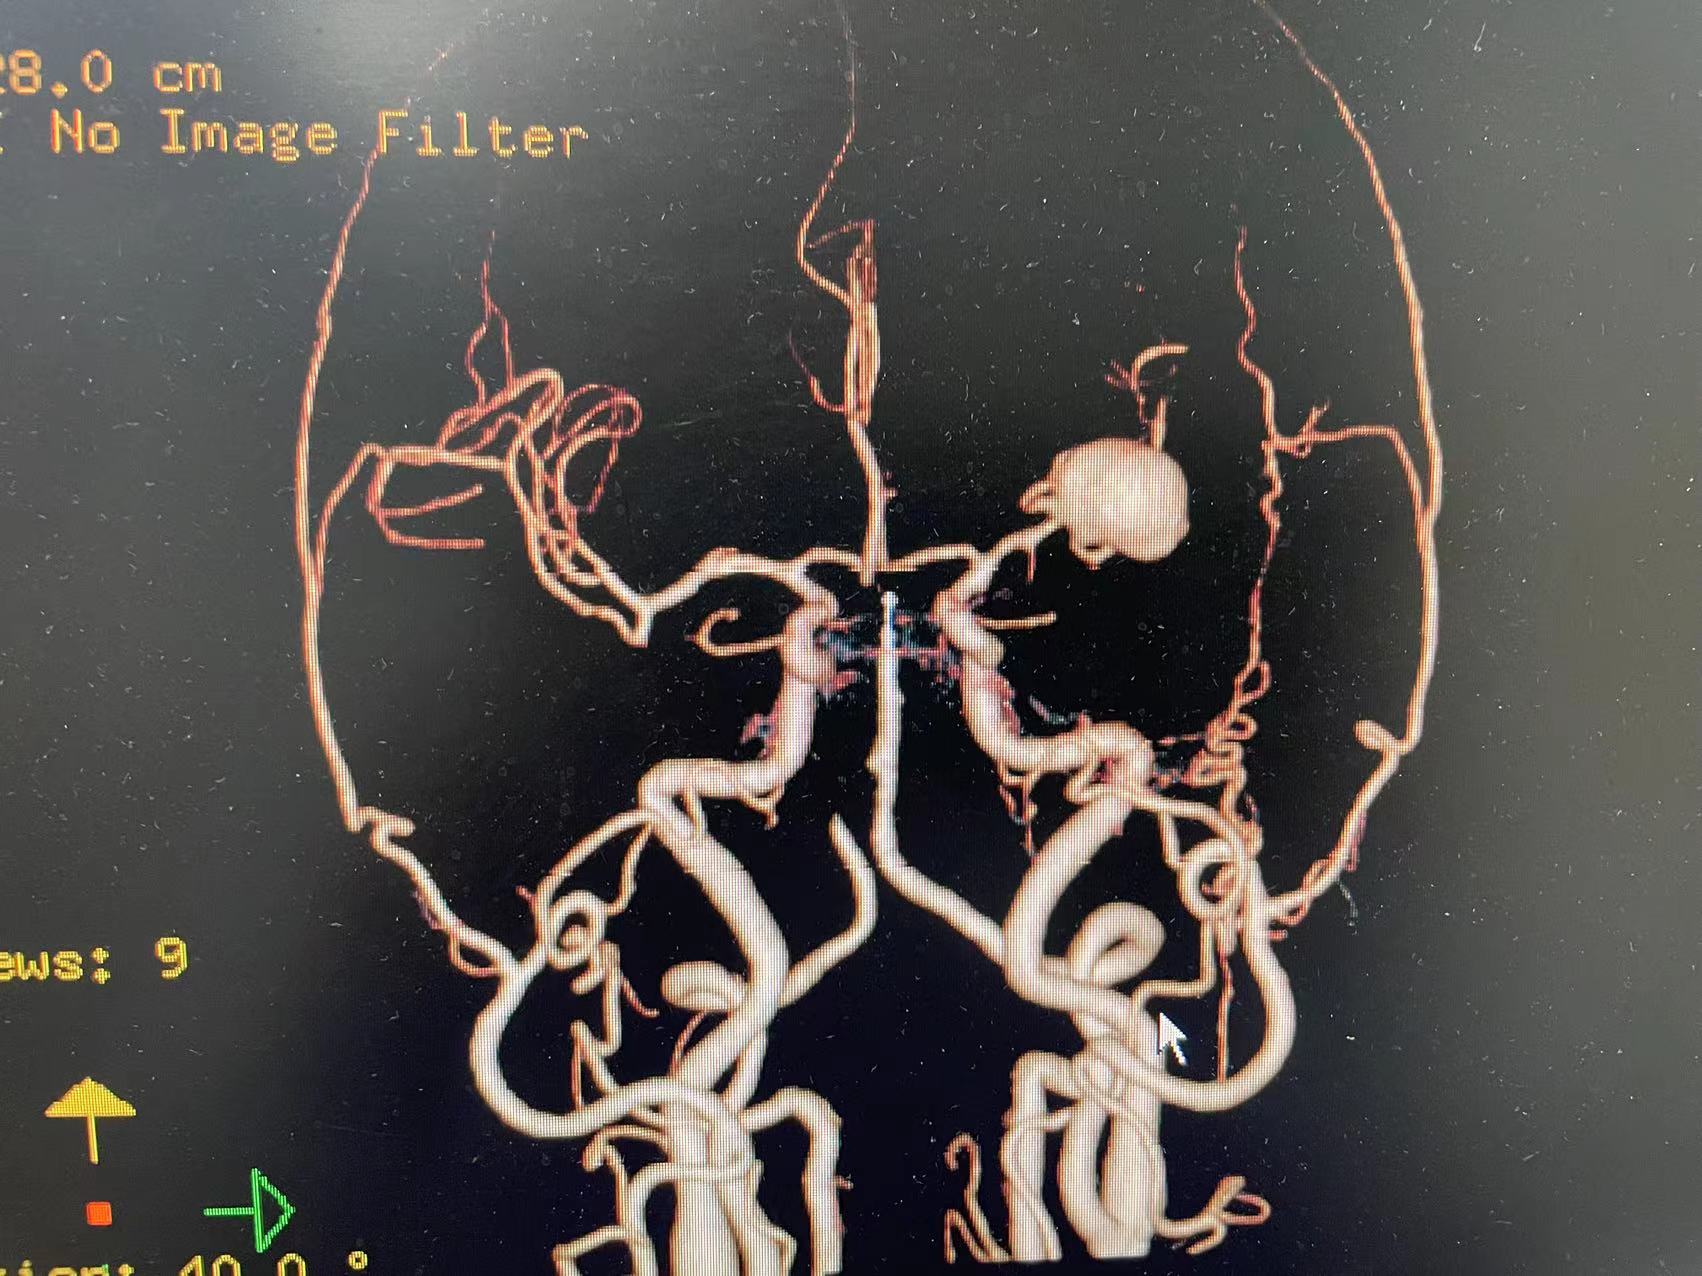

HRQ、女,66岁,463177,因头昏头疼2天,吐词不清1天于20230203日16时24分入院。右侧肢体肌力四级。

指导手术者:成都中医药大学附属医院神经外科主任李定君教授。

夹闭术后两个月,出院后一个月!再次出血,血肿量大,患者清醒!转上级市级医院,拟予介入栓塞后清除血肿

家属选择保守治疗,患者一直清醒!两个月前在华西行介入栓塞术,血肿吸收!

介入栓塞术后两个月来复查!患者清醒轮椅而来,言语稍含糊,右侧下肢肌力可大于三级,上肢一级!